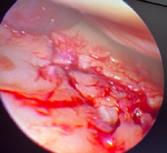

de protezare a genunchiului, cu o evoluție postoperatorie favorabilă, fără complicații. În urma dispensarizării la domiciliu, la 3 săptămâni postoperator, pacientul suferă un traumatism prin cădere de la același nivel, prezentându-se în Serviciul de Urgență tardiv, după aproximativ 10 ore, cu o plagă dehiscentă pe fața anterioară a genunchiului, exteriorizându-se la piele ligamentul rotulian restant, dezinserat de la nivelul polului inferior rotulian. Intraoperator se practica debridare mecano-chirurgicala intensivă, cu îndepărtarea marginilor plăgii, ale țesuturilor necrozate, lavaj intens, abundent și sutura ligamentului rotulian (Fig 1; Fig 2).

Postoperator evoluția este nefavorabilă, cu modificarea markerilor biologici inflamatori (VSH, Fibrinogen, Proteina C-Reactiva ↑), prezența unei hidrartroze restante, pozitive la Staphylococcus aureus meticilino-rezistent (MRSA), ruptura suturii ligamentare, de unde și decizia unei revizii în doi-timpi, conform protocoalelor internaționale și inițializarea antibioticoterapiei țintite cu Linezolid 2mg/ ml, fl II/zi.

În prima etapă s-a îndepărtat proteza primară, s-a practicat debridarea mecano-chirurgicală a țesuturilor neviabile, rezecția ligamentului restant de la nivelul inserției sale tibiale, alezarea canalelor fe-

muro-tibiale, aplicarea perlelor de Stimulan atât in canalele osoase cât și în camera genunchiului, si montarea unui spacer femuro-tibial (Fig 3).